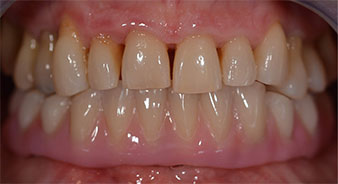

Im Anschluss erfolgt die Abformung und Bissnahme, sodass die Zahntechniker umgehend mit der Anfertigung der provisorischen Arbeit beginnen können. Diese wird im Anschluss am gleichen Tag eingeschraubt (Abb. 17 und 18).

Nach der Zeit, die für die Osseointegration benötigt wird, kann die endgültige Abformung der Implantate erfolgen und entsprechend die endgültige Arbeit angefertigt werden (Abb. 19 und 20). Hier können Behandler und Patient gemeinsam entscheiden, ob diese eine Keramik- oder Kunststoffverblendung, ein Zirkon- oder Metallgerüst bekommen soll. Im vorliegenden Fall hat sich das Team um Dr. Pascu, aufgrund der unklaren Prognose der Oberkieferbezahnung und des elongierten Zahnes 24, für eine Kunststoffverblendung entschieden. Diese ist im Allgemeinen wesentlich einfacher umzustellen und der neuen Situation im Oberkiefer anzupassen.